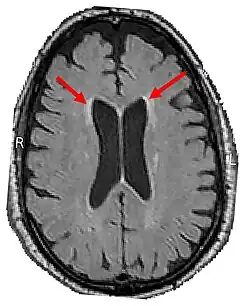

LENAS is seen with damage to the white matter and axons within the brain. The external human LENAS brain shows findings in several major structures. There is mild atrophy of the frontoparietal regions of the brain and a mild reduction of the thalamus and rostral (front) part of the caudate nucleus (which is located in an area of the brain called the basal ganglia).[5] Abnormalities in the frontal, frontoparietal, and temporal lobes are most severe and predominant with LENAS and asymmetry of the cerebral hemispheres has sometimes been found.[5] LENAS also may show moderately enlarged lateral ventricles and atrophy in corticospinal tracts as well as in the pons.[5]

- Brain CT/MRI findings: